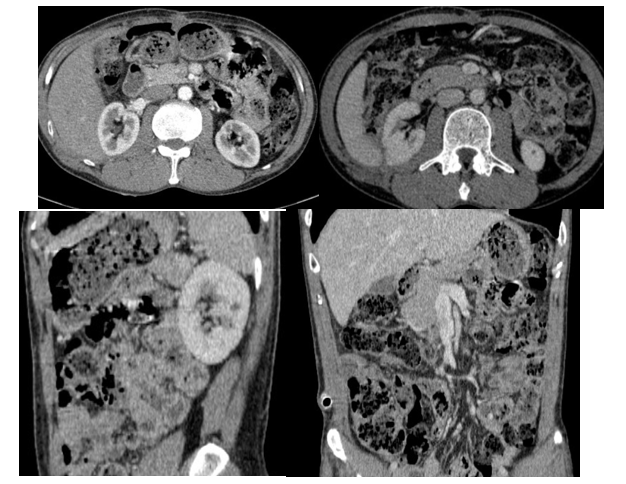

- Hình ảnh chụp cắt lớp vi tính ổ bụng (4/2025): Hình ảnh sau mổ u sau phúc mạc bên phải, hiện thấy tụ ít dịch mỏng, đám thâm nhiễm khoang sau phúc mạc. Ít dịch ổ bụng vùng hạ vị.

Hình 4. Hình ảnh chụp cắt lớp vi tính ổ bụng: sau mổ u sau phúc mạc bên phải, hiện thấy tụ ít dịch mỏng, đám thâm nhiễm khoang sau phúc mạc (sau mổ 1 tháng)